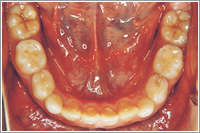

顎を広げると自然に曲がっていた歯が治りました。